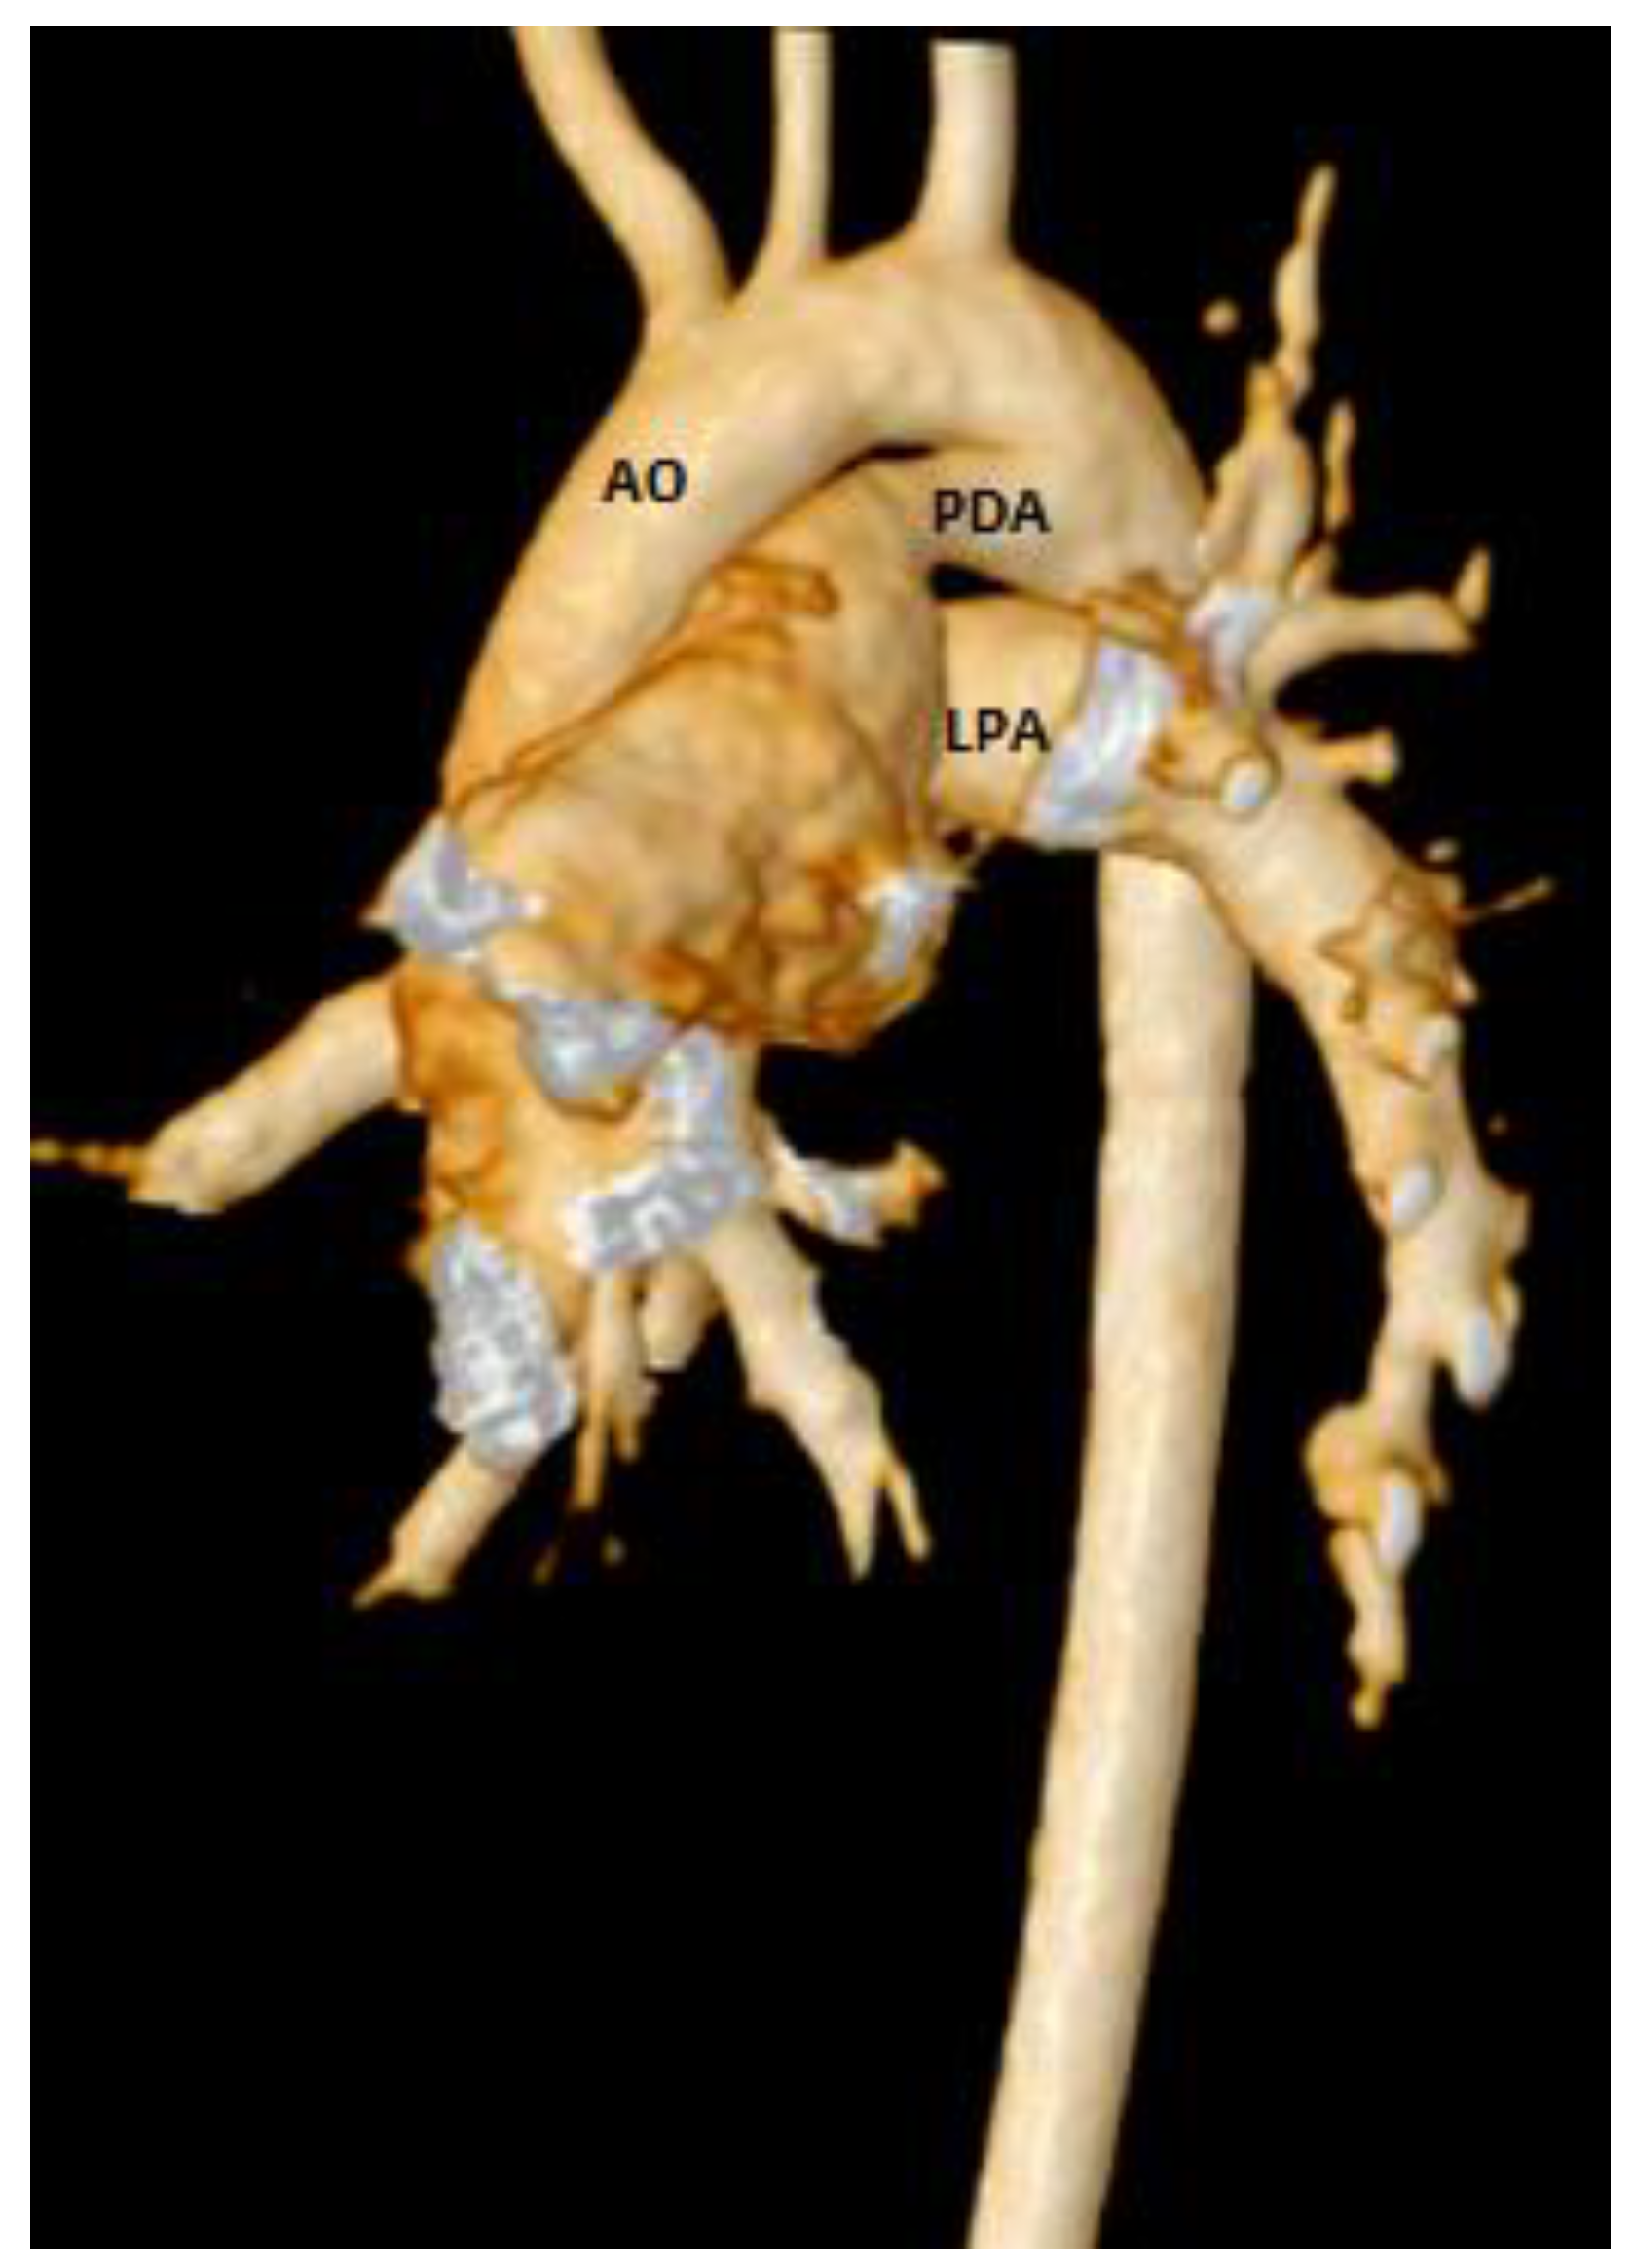

| VSD Flow L/min/m2 | 1.8 | 2.5 |

| PDA Flow L/min/m2 | 1.1 | 1.6 |

| Qp L/min/m2 | 5.4 | 7.8 |

| PVRi Woods U m2 | 8.7 | 6.8 |